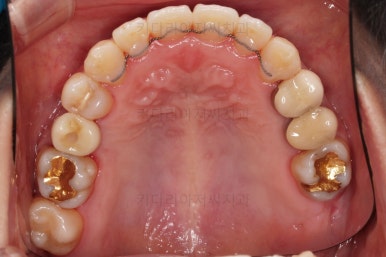

임플란트 보철이 깔끔하게 들어갔고, 교정치료도 마무리가 되었습니다.

화살표 부분은 임플란트가 안들어갔는데요.

약간의 우여곡절이 있긴했었지만 엄밀히 따지면 위아래가 지그재그로 껴들어가는 교합의 특성상 윗니는 1개 모자라도 교합에는 크게 문제가 없답니다.

해당 부분을 임플란트를 해주면 좋겠지만 환자분도 충분히 고민 후에 원하실 때 식립을 하기로 마무리르 하였습니다.

부산연산동치과 전후 사진을 비교해 보겠습니다.

총 22개월 걸렸고, 임플란트는 1개로 마무리를 했습니다.